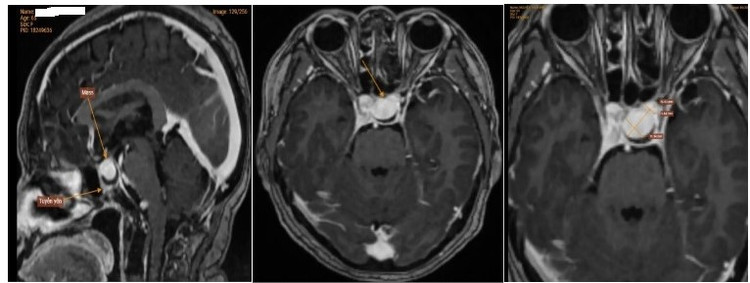

| Nữ bệnh nhân T. có một túi phình kích thước lớn ở động mạch não. Ảnh BVCC |

Kết quả chụp cộng hưởng từ cho thấy, có hình ảnh túi phình lớn ở động mạch não, đoạn xoang hang động mạch cảnh trong trái, chiều cao 16mm, ngang thân 11mm, cổ rộng 7mm. Từ đó, bác sĩ chẩn đoán, bà T. mắc bệnh lý phình động mạch não, rất may túi phình chưa vỡ nhưng cần được can thiệp.